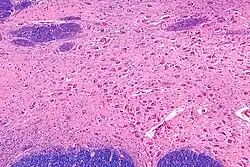

Zajímavou a nebezpečnou roli má acetylcholin ve střevě, kde existují speciální acetylcholinové receptory, jež podporují buněčný růst (což může vést v patologických případech až k rakovinnému bujení).[1]